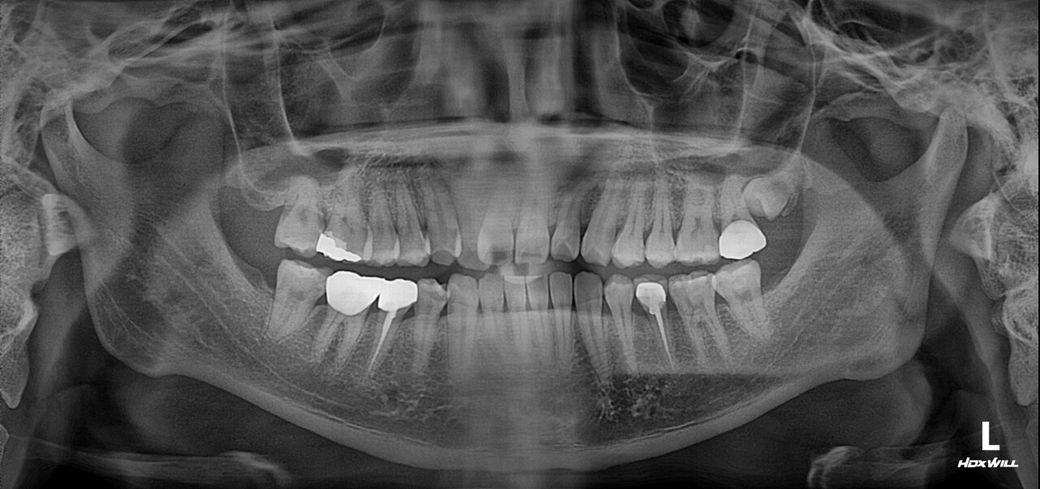

치과 각 진단이 상이한데 어떻게 하면 좋을까요?

단거 먹거나 그러면 이빨 시린곳 한군데 있거든요?

• 1번 째 사진

• 2번 째 사진

해당 치아에 대한 진단 자체는 다를 수 있어 보입니다. 아마 2번째 지켜보자는 곳도 시간이 지나면 신경치료를 고지할 가능성이 큽니다. 해당 치아는 이미 치료를 했는데 시린 증상이 나타나고 있기 때문에 시린 증상이 있다면 보철물을 제거하고 신경치료를 하는 것이 맞습니다. 즉 1~3군데 모두 진단 및 치료 방법 자체가 다른 것은 아닙니다.

사진으로 봤을 경우에 보철물과 치아 사이에 음영이 보이는것로 봐서는 충치일수도 있지만 아닐수도 있습니다 .

육안으로 보철물과 치아 사이의 경계부위를 확인해 보거나 보철물을 제거해 보기 전에는 확신을 하기 힘들어 보여요.

사진상으로 보면 어금니 사이에 충치가 있는것같습니다. 일반적으로 사이에 충치가 있다면 인레이치료를 하게 됩니다. 증상이 있으셔서 제거해봐야 알겟지만, 인레이 치료는 신경치료 가능성이 있습니다. 치료를 받으시긴 받으셔야될것같습니다.